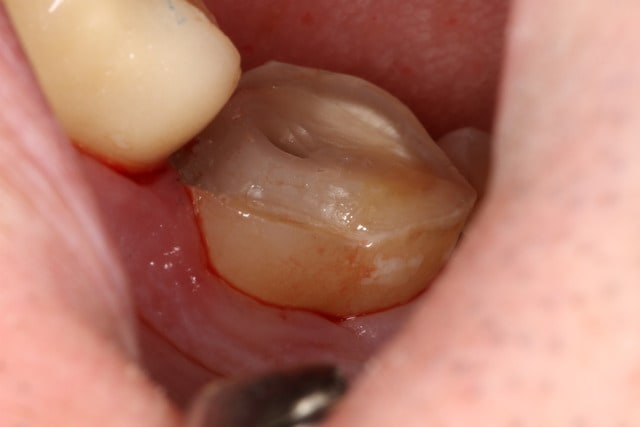

Une prep, pas encore posée :

2015 08 14 14.57 - Eugenol

2015 08 14 15.15 - Eugenol

2015 08 14 15.34 - Eugenol

2015 08 14 15.40 - Eugenol